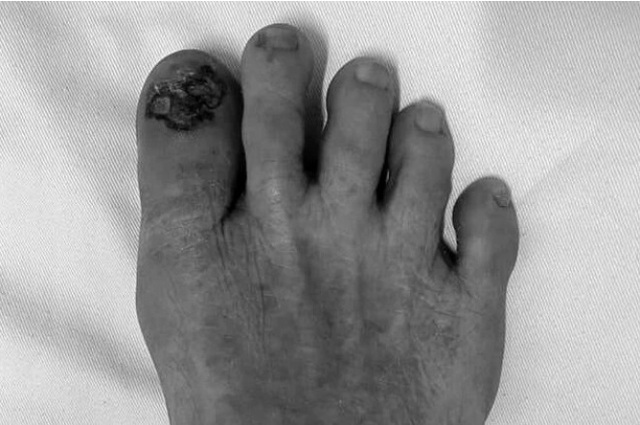

Znews đưa tin, bà L.T.P. (68 tuổi, Thanh Hoá) đến khám tại khoa Phẫu thuật Tạo hình thẩm mỹ và Phục hồi chức năng, Bệnh viện Da liễu Trung ương (Hà Nội). Triệu chứng ban đầu là ngón chân có mảng màu đen, loét, rỉ dịch, chảy máu và đau nhẹ.

Trước đó, bà P. đi khám và điều trị ở nhiều nơi nhưng không đỡ. Vệt đen này đã xuất hiện khoảng 2 năm. Theo thời gian, tổn thương màu đen tăng dần về kích thước, không đau, sần sùi và loét rỉ dịch.

Vừa qua, bà P. đến Bệnh viện Da liễu Trung ương khám. Sau khi làm hàng loạt xét nghiệm chuyên khoa, bà được phát hiện sớm những dấu hiệu ung thư da với chẩn đoán sơ bộ là ung thư tế bào hắc tố.

Bệnh nhân được chỉ định nhập viện để cắt toàn bộ tổn thương màu đen và xét nghiệm mô bệnh học. Sau vài ngày, kết quả giải phẫu bệnh khẳng định bà P. mắc ung thư tế bào hắc tố.

Tổn thương có thể hình thành nốt, loét hoặc chảy máu, có thể biểu hiện dưới dạng khối u dưới móng, tách móng hoặc trông giống như hạt cơm dưới móng. Đồng thời, có thể gây loạn dưỡng móng (móng mỏng, nứt hoặc biến dạng móng). Nếu khối u xâm lấn xương có thể gây đau.

Dấu hiệu nhận biết ung thư tế bào hắc tố là các tổn thương màu đen. Theo thời gian, các tổn thương này tiến triển về kích thước, không đồng nhất về màu sắc bất kỳ vị trí nào. Đối với người Việt Nam, các vết này thường xuất hiện tại các vị trí đầu ngón chân, ngón tay.